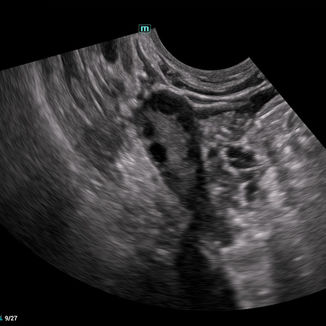

Excellent Imaging Technology

Dedicated to improve scanning efficiency with more accuracy and consistency for Obstetrics and Gynecology applications.